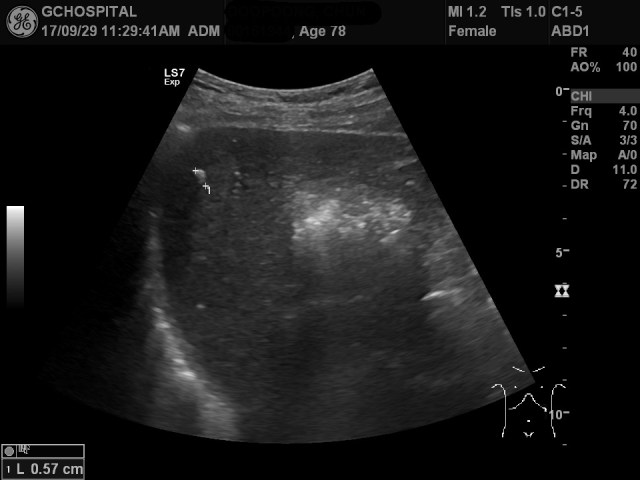

마지막까지 간의 지붕부위를 보기 위해 노력해서 얻은게 위 영상입니다. 간의 지붕부위가 여전히 잘 그려지지 않을뿐 아니라, 앞서 CT에서 보였던 1센티미터 크기의 낭종도 보이지 않습니다. 간내석회화는 하나를 찾아서 표시를 했지만, 이 병변이 정말로 석회화음영인지 또한 후방에코음영이 보이지 않으므로 확실하다고 할 수 없는 상황입니다.

이 검사를 한 때는 작년 상반기였습니다. 이처럼 좌측측와위 자세에서 갈비뼈 사이로 탐촉자를 위치하는 것만으로는 간의 지붕부위 및 간우엽을 제대로 보는게 어려웠던 사례가 종종 있었기 때문에 지금처럼 좌측 측와위 이외의 다양한 자세를 시도하게 되었습니다.